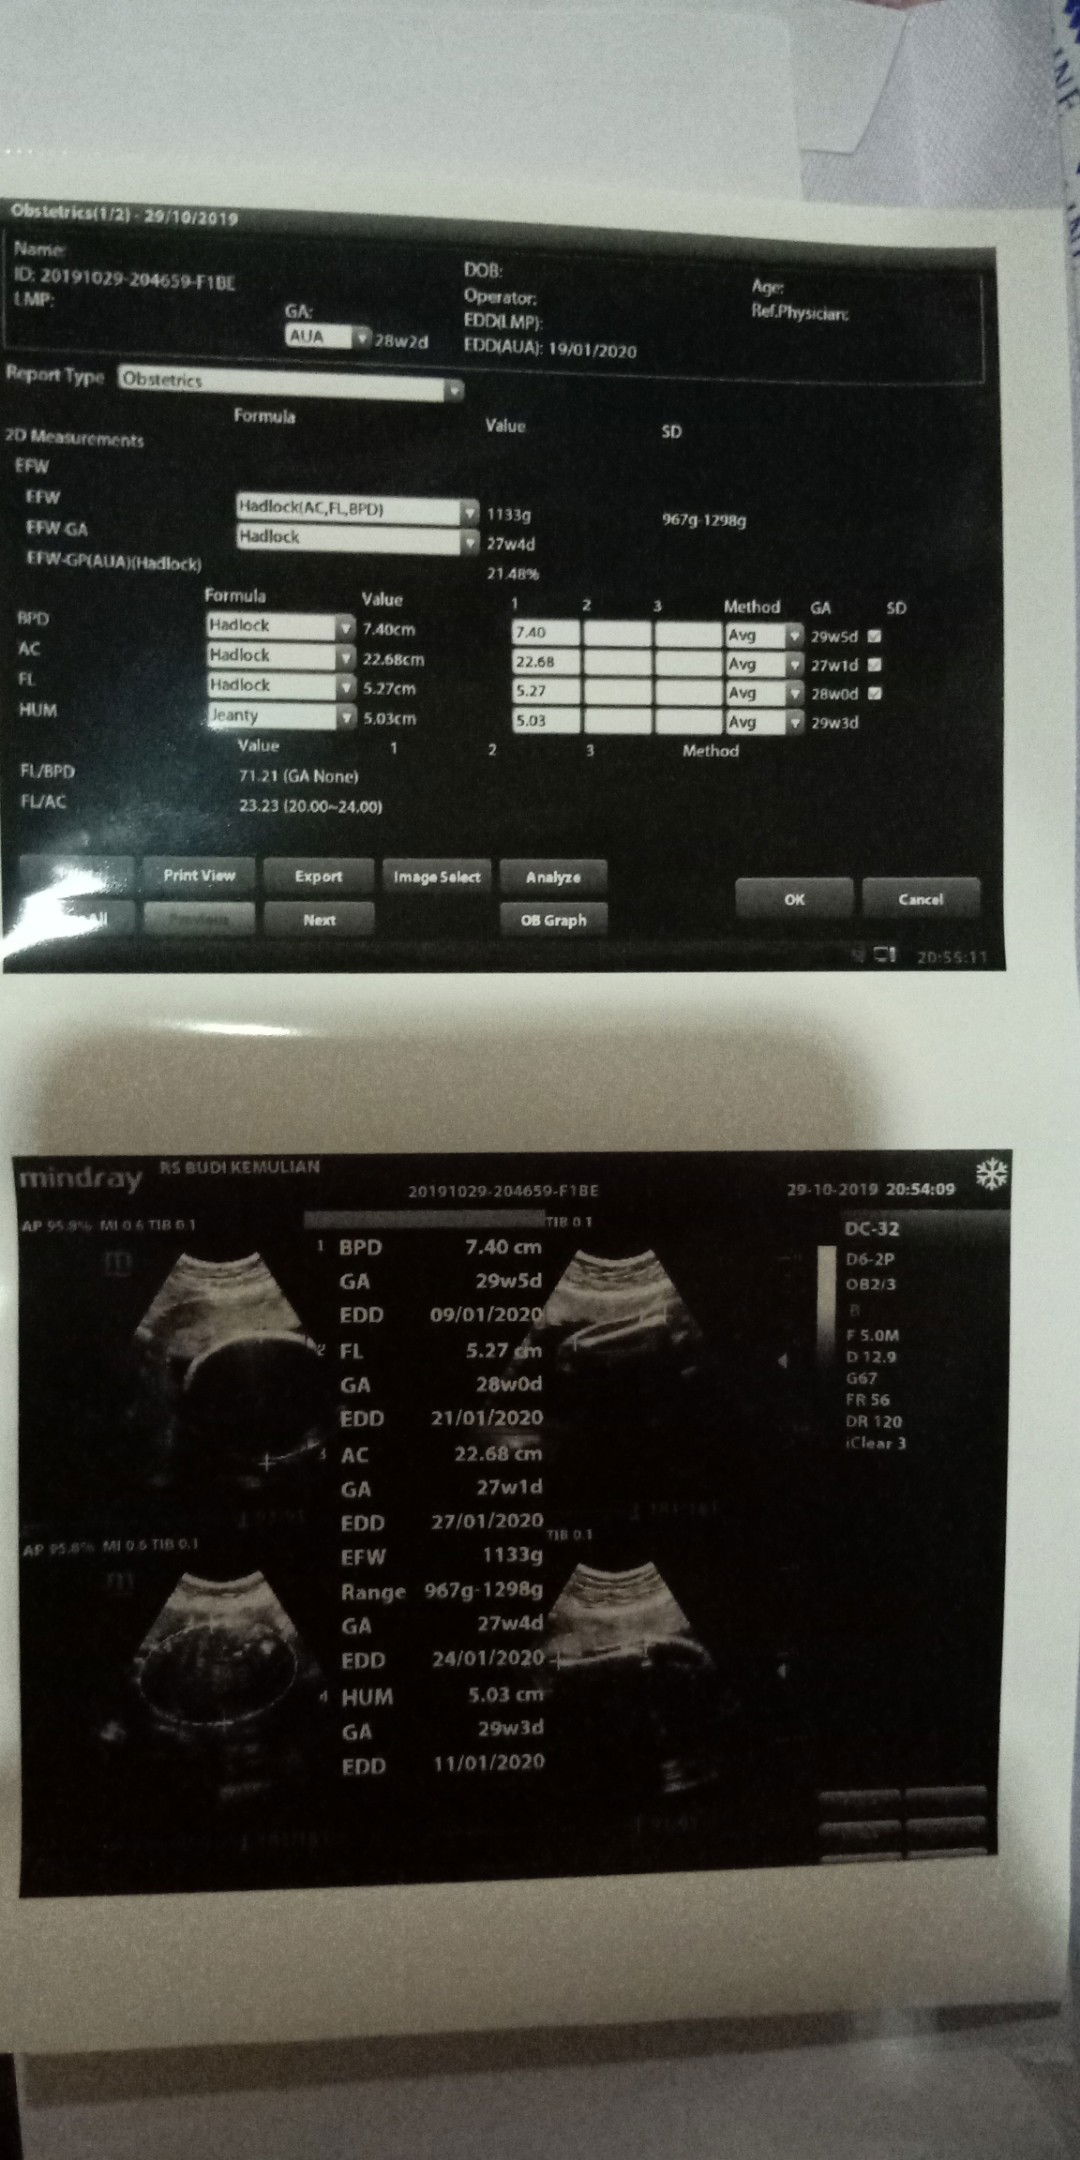

Pregnant 28 weak